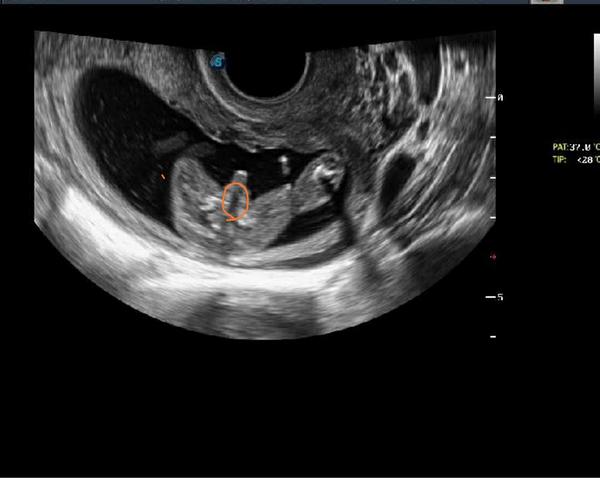

Dobrý den, podle uzt a doktorky čekáme 100%kluka. Já tam ale stejně vidím jakoby kávové zrno (co mají holky), štěrbinku 🙂) , myslíte že by byla ještě možnost, že by z toho byla holka. Jsem 16tt. Děkuji za názory 😉

Ja myslím že tady na tom utz je to úplně jasné že je to kluk , většinou co tu holky dávají mazanice nepoznám fakt ani prd , ale tohle je víc než jasný

@adelaide131 Mne to teda pripada jako ukazovy pindik, ale nejsem doktorka. Kazdopadme v 16tt uz bych ji verila. Ja takhle doufala ctyrikrat, ze to je jen pupecni snura 😉🙂

Taky bych rekla jasny chlapecek. V tomto tydnu, pokud je takova to fotka, uz ma doktorka jasno 🙂

Když doktor v 16tt vidí na ultrazvuku na 100% kluka, tak my tady opravdu neuvidíme holcicku 😃 V dnešní době se málokdy spletou, to se stávalo před 25lety.. Jinak, ale touhu po holčičce naprosto chapu😉